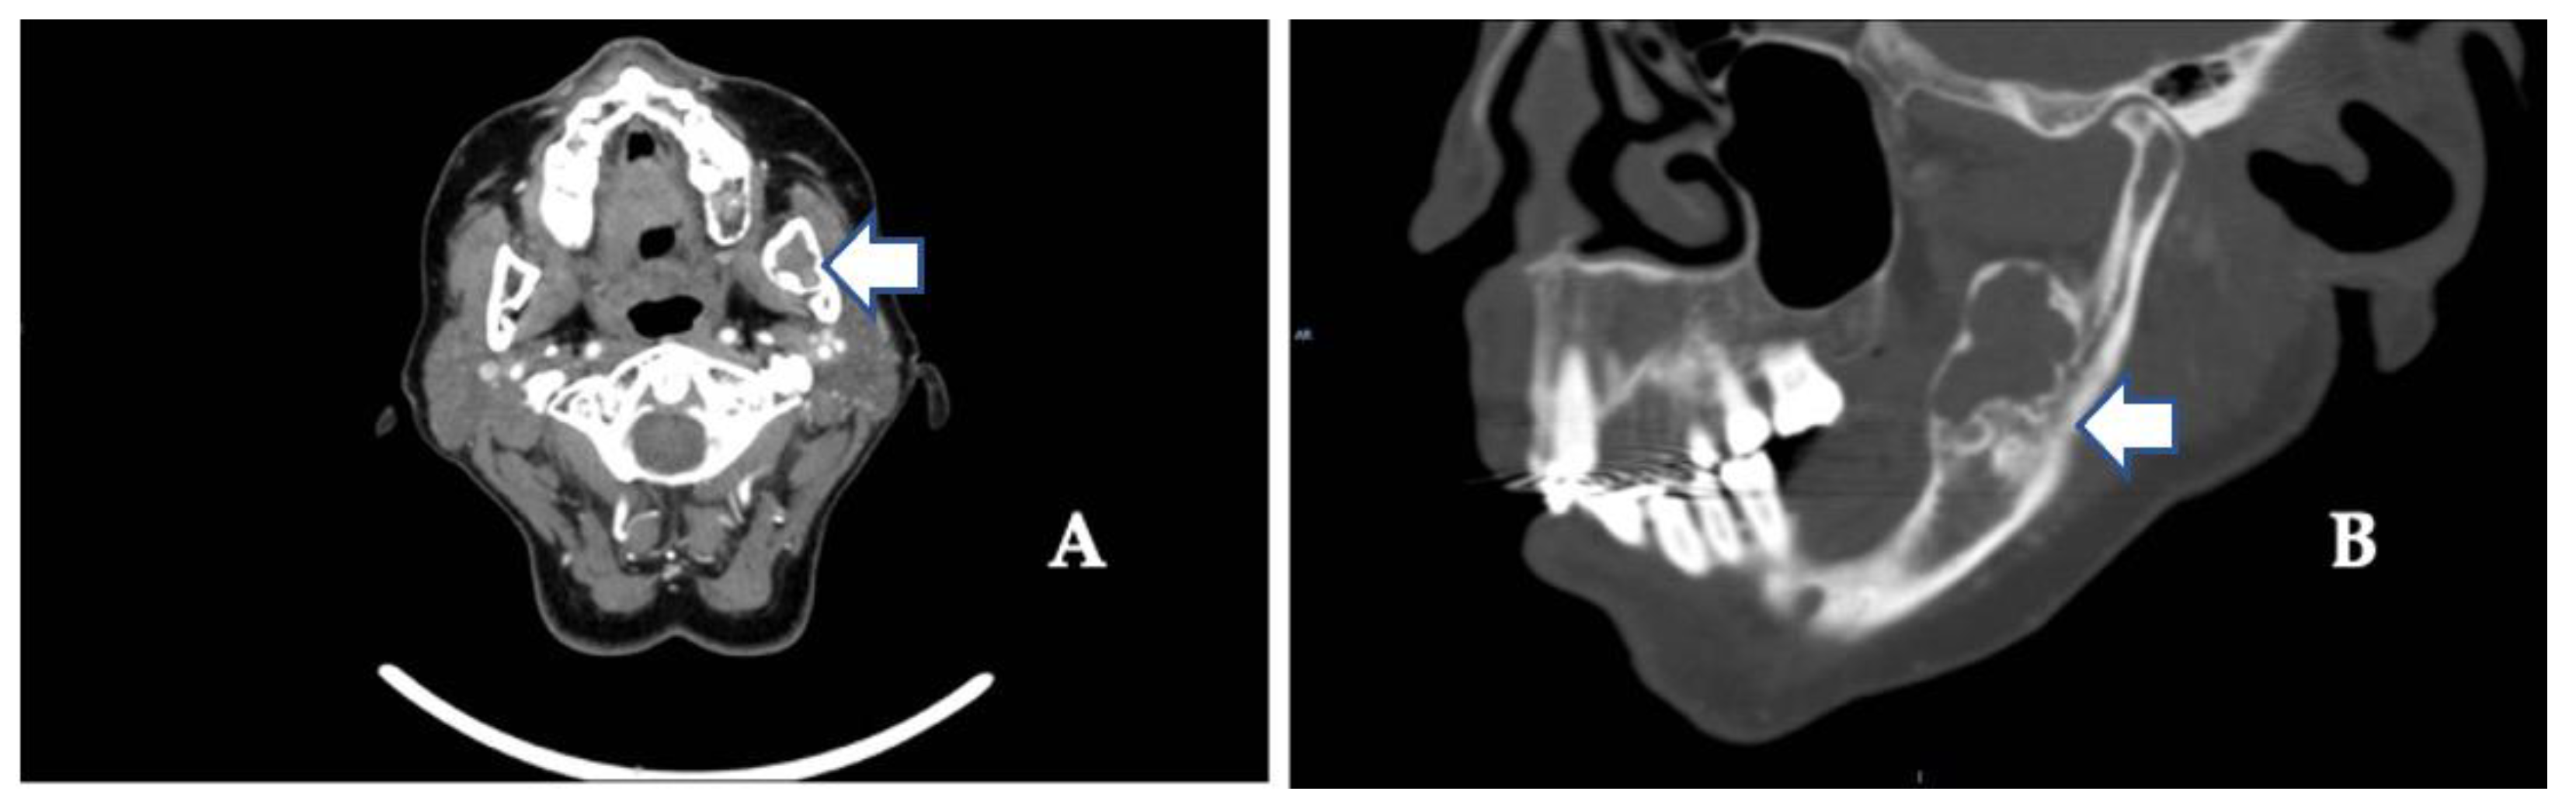

The usual diagnostic imaging study with a panoramic radiograph showed a well-defined mixed radiolucent–radiopaque lesion with peripheral enhancement in the left mandibular ramus occupying almost its entire thickness (Figure 1). Computed tomography performed with contrast was used to confirm the existence of a heterogeneously enhancing 3 cm long tumor with lobulated margins and bicortical expansion without bone perforation. Radiographically, there appeared to be an expansile cystic mass with areas of calcification and sclerotic borders. The mandibular lower border was intact (Figure 2A,B).

Figure 2.

(A) Contrast-enhanced computed tomography scan showing the extent of the tumor along the mandibular angle (see arrow) (coronal image). (B) Sagittal view shows mixed radiolucent–radiopaque lesions (see arrows) and advanced osteoarthritic changes in the left temporomandibular joint (see arrow).